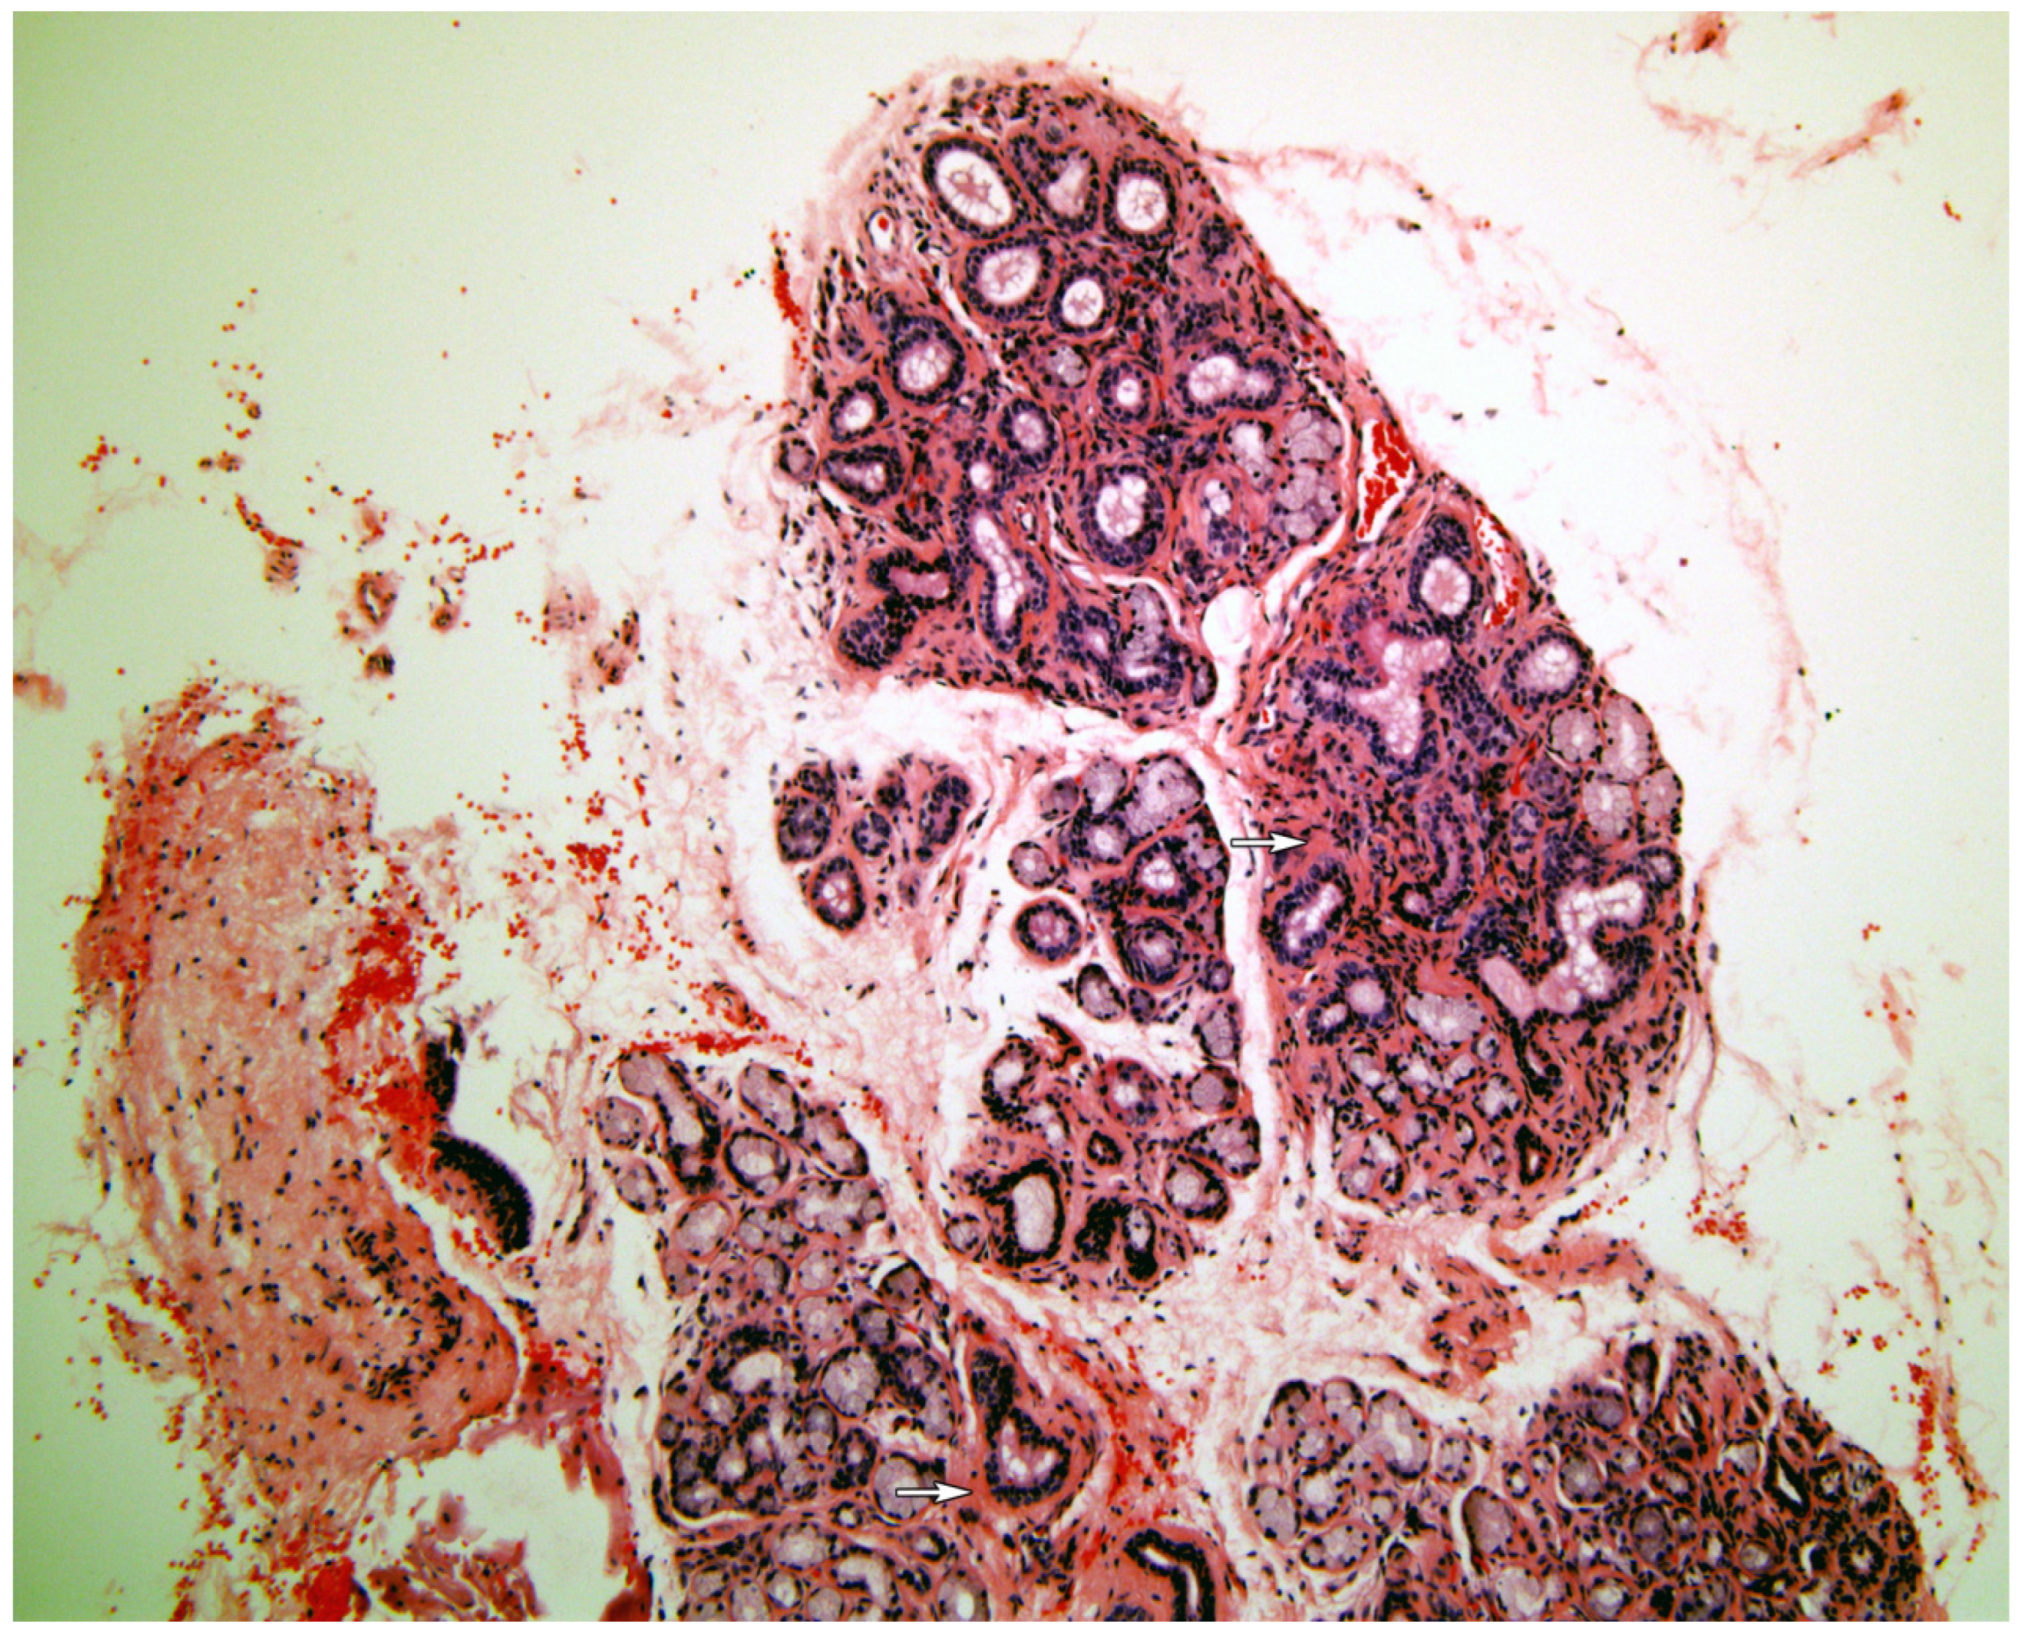

Figure 1, Figure 2, Figure 3, Figure 4 and Figure 5 present typical findings of normal morphology (Figure 1), SS (Figure 2), focal acinar atrophy (Figure 3), severe atrophy and fibrosis (Figure 4) and fatty replacement (Figure 5).

Figure 2. The normal gland structure is preserved, with focal inflammatory.infiltrate (arrows), typical for Sjögren syndrome(Hematoxylin and Eosin, original magnification ×40).